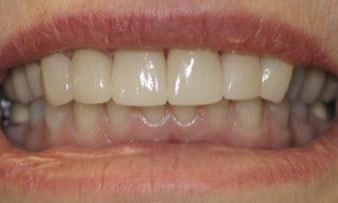

Smile Gallery

Are you considering dentistry at Michael J Nelson DDS? If so, we’d like to invite you to browse our Smile Gallery. Our dental team can improve your oral health and help you attain the attractive smile you’ve always wanted.